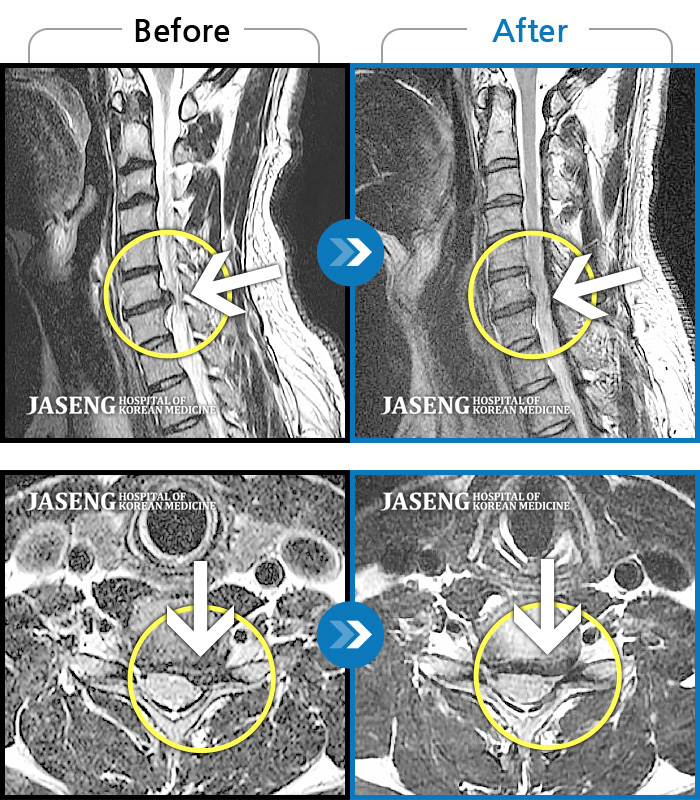

목디스크

강남 · 강만호 원장

양측 승모근 통증과 목 통증, 견갑골 통증으로 고개를 돌릴때 통증을 호소하는 환자였습니다.

촬영시기

2019.11.18 ~ 2024.07.30

2024.08.09

조회수 480